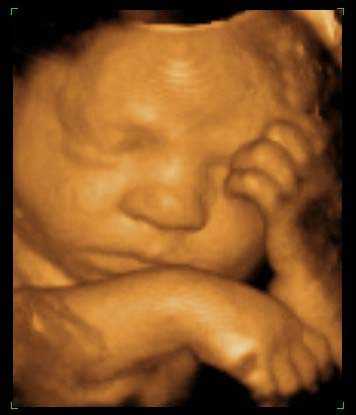

Вашему малышу уже 35 неделек. Он не только сформировался и вырос, но и стал абсолютно уникальным: имеет неповторимый рисунок кожи и индивидуальные черты лица.

Сейчас детка весит уже в среднем 2 400 г, но этот показатель может отличаться в каждом отдельном случае. Начиная с 35 недели беременности, ребеночек очень быстро набирает вес, тяжелея каждую неделю на 200-220 г. Его рост может превышать уже 46 см – конечно, в утробе достаточно тесно, и вы четко ощущаете каждое шевеление.

Продолжает накапливаться подкожная клетчатка, сейчас наиболее интенсивно – в области плечиков. К рождению кроха станет красивым и пухленьким, кожица гладкая, ровная, приятно розовая, круглые щечки, достаточно длинные волосики. Впрочем, бывают и почти лысые младенцы – все это индивидуально.

Сейчас у вашего пузожителя уже достаточно длинные ноготки, и он даже может нечаянно поцарапаться. То, что кроха свернут калачиком, да еще и вверх ногами, абсолютно не доставляет ему никакого дискомфорта. А вот животик может приносить ряд неудобств маме.

Сейчас главным образом идет накопление жировой и мышечной ткани. На последних сроках малыш набирает до 220 г каждую неделю. Его вес на 35 неделе беременности составляет в среднем 2400-2500 г, а размер (полный рост) доходит до 47 см, но, конечно же, эти данные очень индивидуальные и не в последнюю очередь зависят от генов. Ваш ребеночек вообще уникален: уже оформился неповторимый рисунок его кожи, и все черты лица в целом отличаются индивидуальностью. Правда, глаза у всех деток сейчас серо-голубые, но это еще не окончательный их цвет.

Кожица малыша постепенно разглаживается и приобретает приятный розоватый оттенок, с тела исчезает пушок лануго. На 35 неделе беременности главным образом округляются плечики. Совсем скоро детка начнет опускаться, прижимаясь головкой и плечами вниз. Сейчас он устраивается поудобнее, занимая положение, в котором будет рождаться. В животике уже явно маловато места, движения крохи достаточно скованы, он может даже поцарапаться нечаянно (ноготки достаточно длинные). Но в целом, несмотря на тесноту и в большинстве случаев перевернутое вверх тормашками состояние, ребеночку очень комфортно в мамином лоне. Чего не скажешь о самой маме…